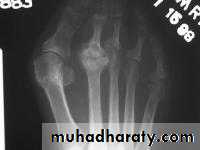

While radiographs are not essential, they usually are obtained. Radiographs show fragmentation of the tibial tubercle apophysis and, at times, a separate ossicle.